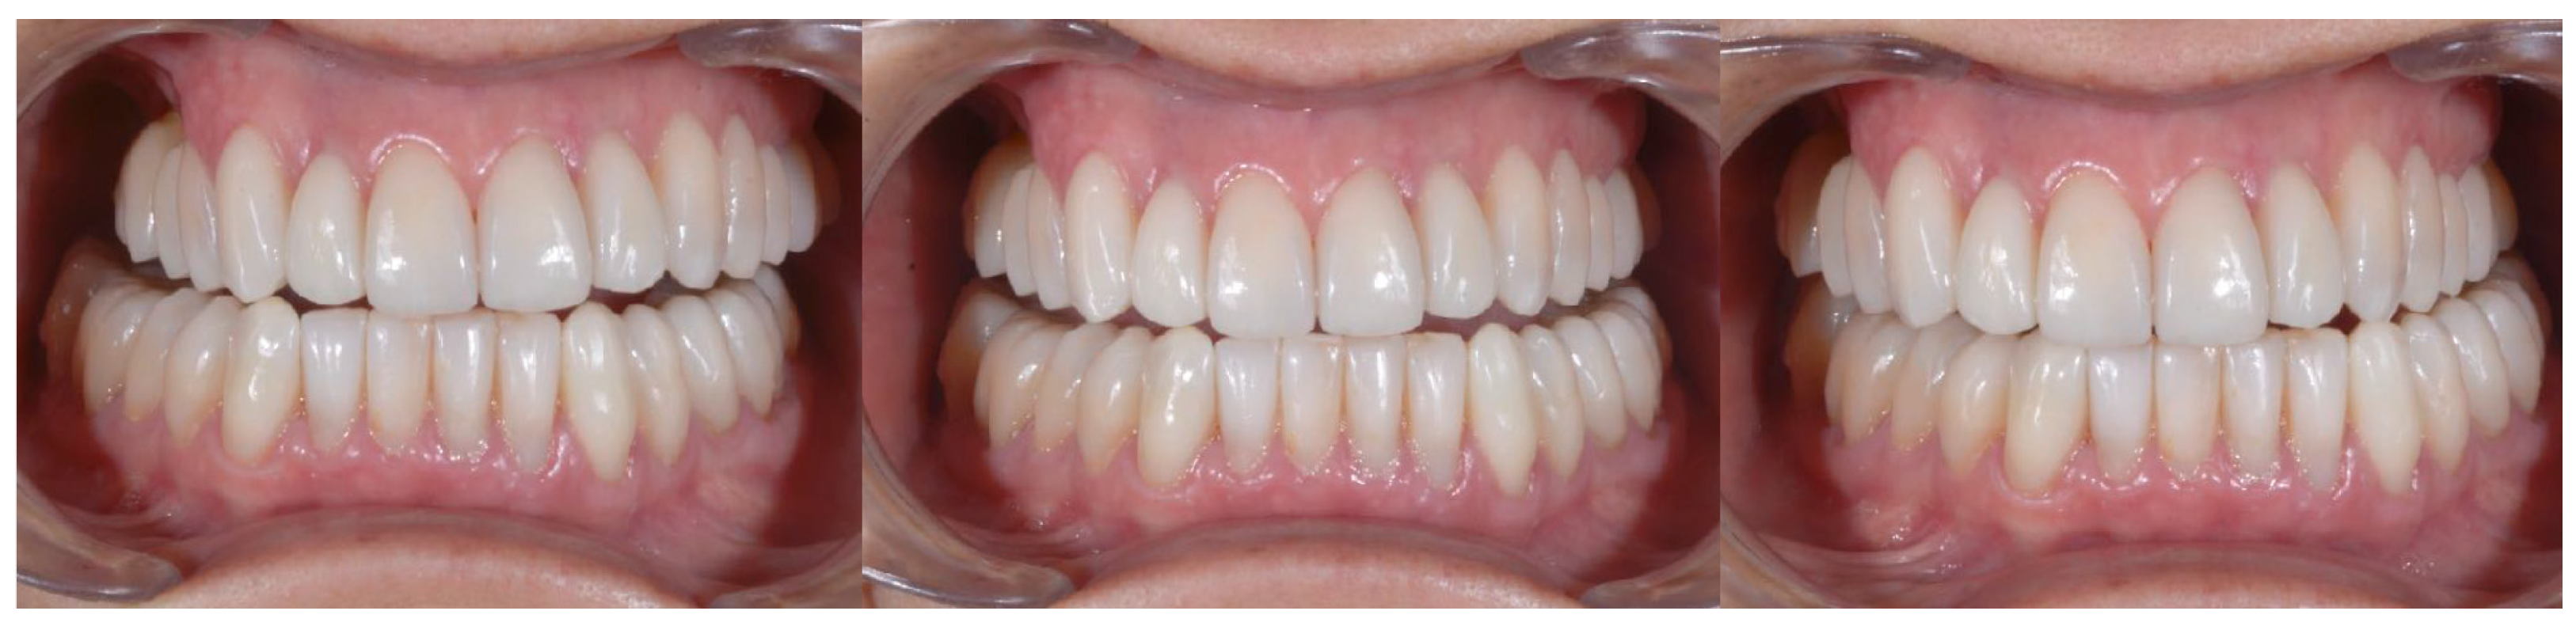

2.2. Clinical Example

2.3. Outcome Achieved